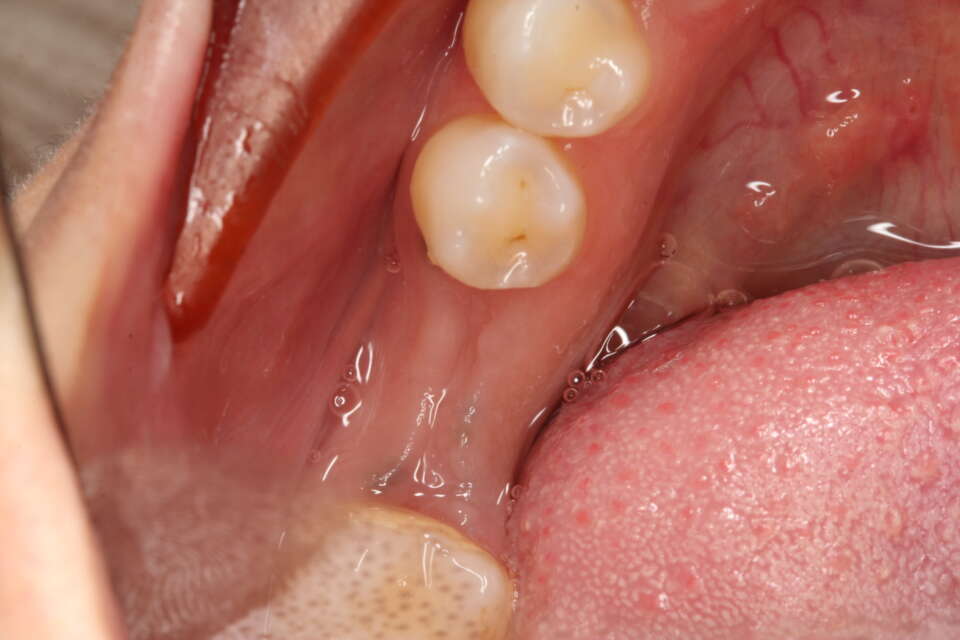

IMG 8705

IMG 7646

The soft tissues really like zirconia and just look how natural the new tooth looks